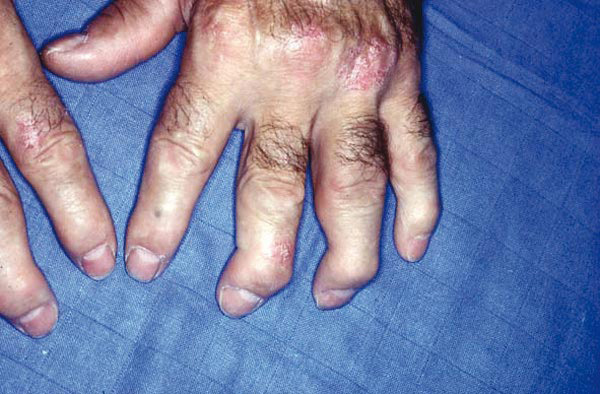

Le tableau clinique typique est constitué, chez une personne atteinte de psoriasis, par la survenue de douleurs articulaires d’horaire inflammatoire, révélant des arthrites périphériques, de forme oligoarticulaires et asymétriques le plus souvent, et pouvant atteindre les articulations interphalangiennes distales (fig. 1 et 2). Les manifestations cutanées du RP comprennent le psoriasis (généralement psoriasis en plaques) et le psoriasis unguéal, souvent marqué par un épaississement de l’ongle ressemblant à une mycose.